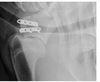

Figure 98-9. Mediolateral (left) and craniocaudal radiographic views of supraglenoid tubercle fracture repaired with the help of a human distal femoral LCP.